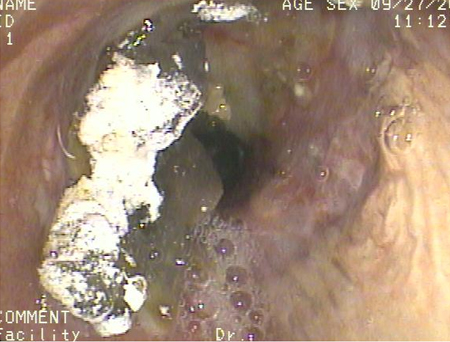

[Figure caption and citation for the preceding image starts]: Broncoscopia mostrando aspiração de bário para o brônquio principal direito depois de um estudo de esofagografia baritada em um paciente com pulmão transplantadoDo acervo de Dr. Kamran Mahmood [Citation ends].